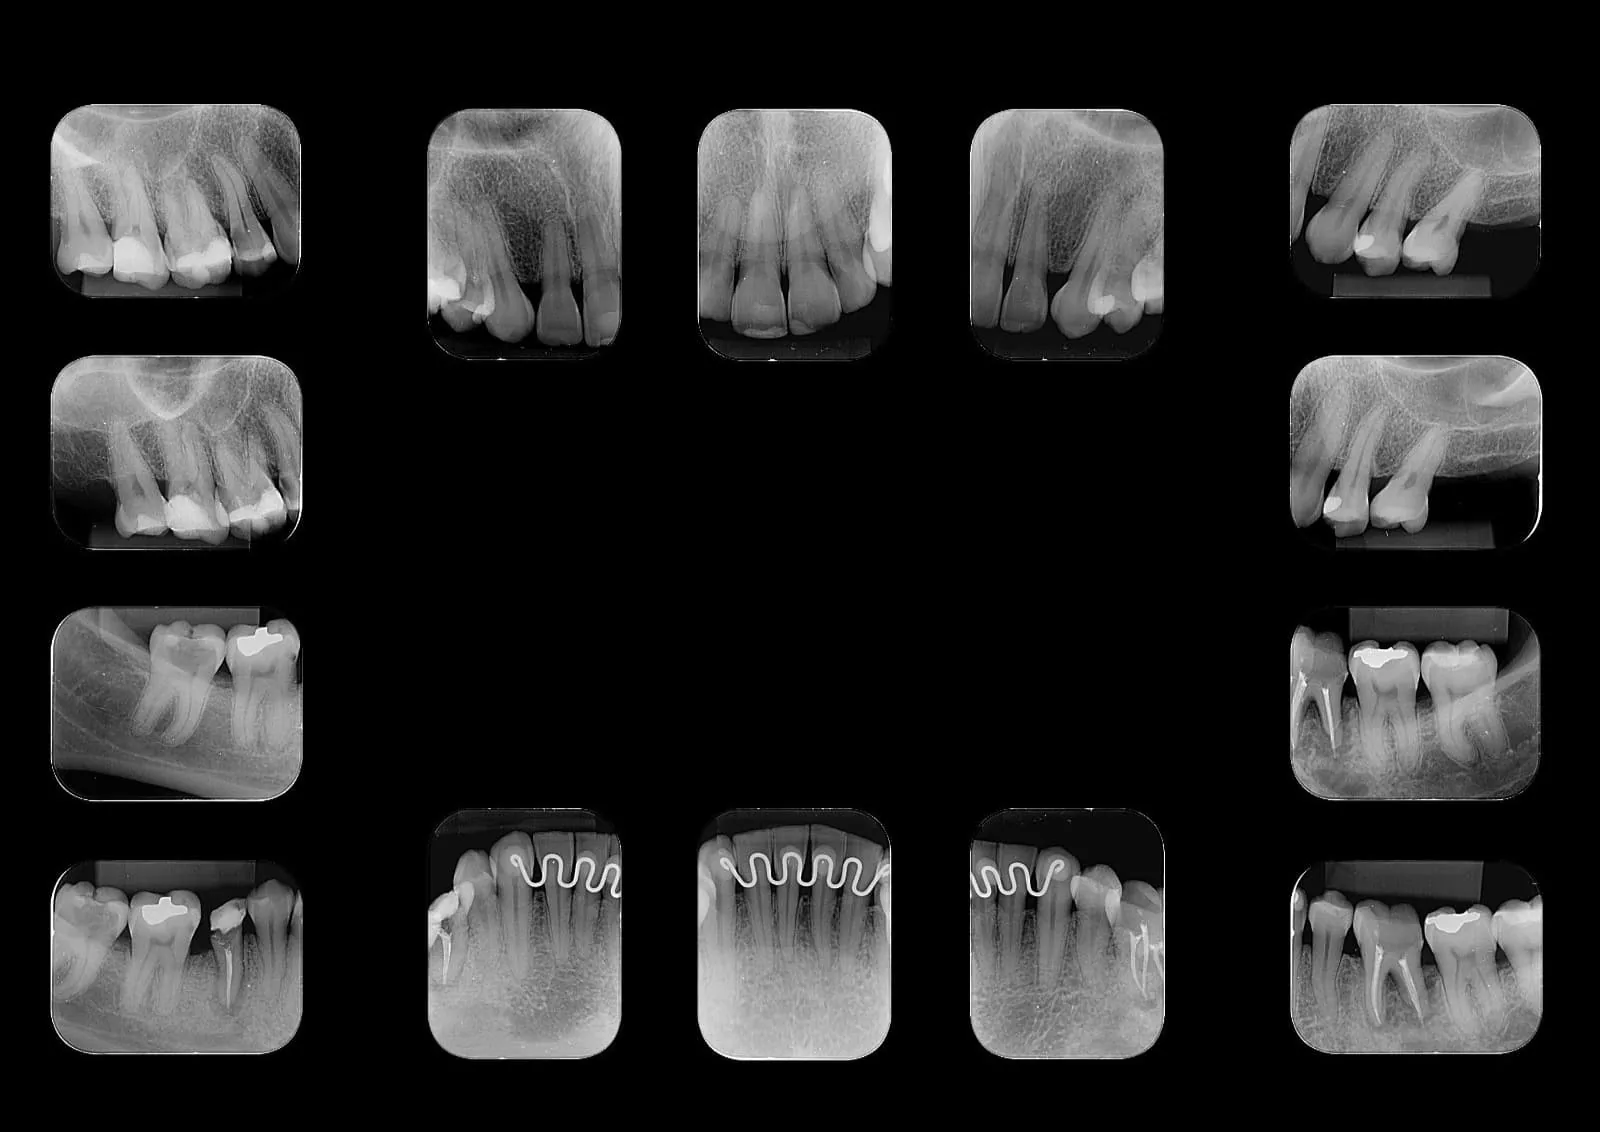

Periapical Boca Toda

Também conhecida como levantamento periapical completo, é um conjunto de radiografias intraorais que permite a avaliação detalhada de todos os dentes e de suas estruturas de suporte.

O exame é composto por 14 radiografias periapicais:

- 7 da arcada superior (maxila)

- 7 da arcada inferior (mandíbula)

As imagens são obtidas por meio de pequenos sensores digitais posicionados no interior da cavidade bucal, proporcionando alta definição e riqueza de detalhes das estruturas dentárias e do tecido ósseo adjacente.

Para pacientes com dentição decídua (dentes de leite), o exame é realizado com 10 radiografias periapicais (5 superiores + 5 inferiores).

Indicações

- Lesões cariosas

- Reabsorções ósseas interdentais

- Alterações periapicais (granulomas e cistos)

- Avaliação do periodonto e estruturas de suporte

Qual a diferença entre radiografia periapical e panorâmica?

A radiografia periapical é intraoral e mostra de 1 a 4 dentes em alta definição, sendo ideal para diagnóstico de canais, lesões cariosas e granulomas.